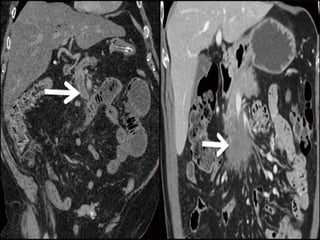

Specific CT signs

 Thromboembolism in the mesenteric

vessels

 Lack of bowel enhancement

 Circumferential bowel wall thickening:

-Target sign

 Intramural gas

 Portal vein gas

 Focal / diffuse bowel dilatation

 Bowel obstruction

 Increased attenuation of mesenteric fat (edema)

 Vascular engorgement

 Variable enhancement pattern

 Ascites

Nonspecific CT signs

Signs of bowel gangrene:

 Large amount of intraperitoneal fluid

 Gas in the mesenteric / portal vessels

 Thinned bowel wall with poor or absent

enhancement

Paper thin bowel wall

White attenuation Grey attenuation

Water target sign Pneumatosis intestinalis